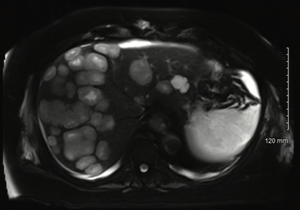

Ghulam Gous, MD, and colleagues report a case of glioblastoma with extensive liver metastases along with a review of previous reports of liver metastasis from glioblastomas and the possible mechanisms of metastasis.